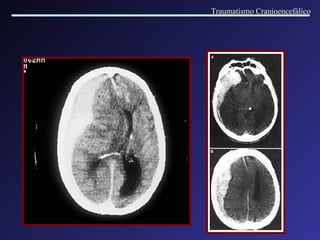

Hematoma Intracerebral tardio, evoluindo a partir da área de contusão hem o rrágica na região fronto-parietal E. Note-se na região frontal D, hematoma frontal  tardio que estava anteriormente normal . Hematoma Intracerebral frontal bilateral tardio a partir de TC inicial normal. Traumatismo Cranioencefálico

Contusões múltiplas e hematomas intracerebrais Densidade mista: múltiplas áreas de hemorragia com edema perilesional. Traumatismo Cranioencefálico